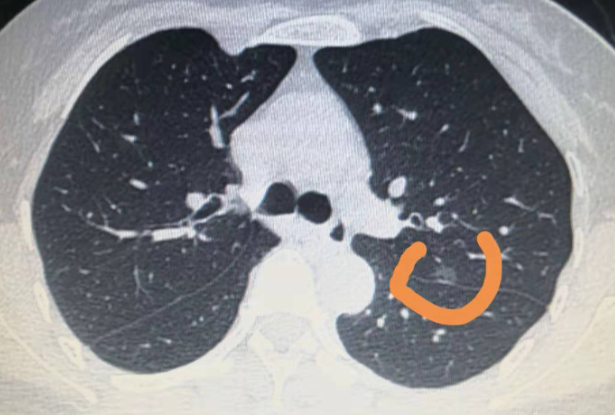

肺部结节一般没有特别明显的表现症状,只有在做检查时才会确诊,当身体出现了肺部结节时,就表示肺部出现了某些疾病,需要引起重视,故而肺部结节的病因有很多,只有搞清楚发病的病因,才能根据病因治疗结节。下面就一起去了解一下造成肺部结节的原因有哪些。

2、起肺部结节的原因还包括感染因素,比如身体受到了结核菌,蛔虫病,细菌性脓肿等病毒和细菌的感染,就容易产生肺部结节以及别的肺部疾病出现。还有就是,血管发生了病变也是导致肺部结节的原因之一,当肺部里面的血管发生了海绵血管瘤肺动脉畸形,或者是毛细血管扩张等病变,那么就可能形成结节。

3、引起肺部结节最主要的原因就是恶性疾病,比如患上了原发性的小细胞肺癌,乳腺癌,结肠癌,肉瘤等转移性的恶性肿瘤,就会导致肺部组织和细胞受到损伤,然后影响到肺部功能,最后就可表现为肺部结节。